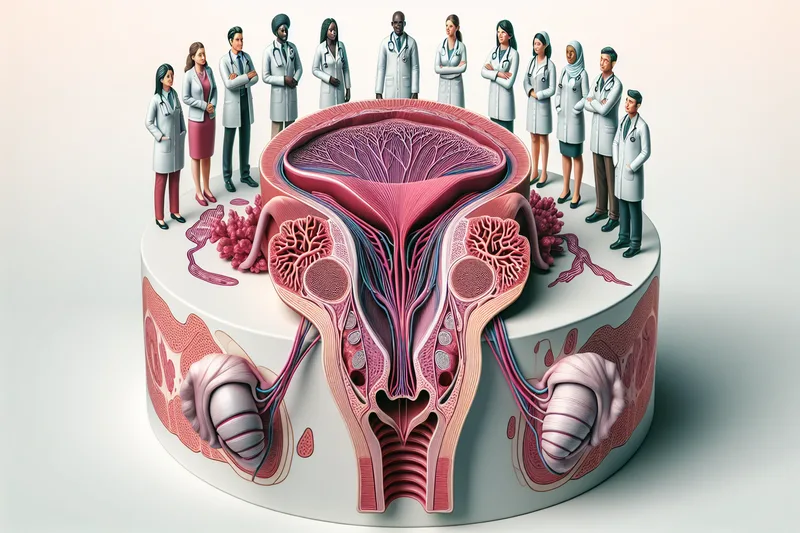

Anatomie du plaisir : comprendre les mécanismes

Pour comprendre le plaisir clitoridien, il est nécessaire de connaître l'anatomie complète du clitoris. Contrairement à ce que suggèrent encore de nombreux manuels, la partie visible — le gland clitoridien — ne représente qu'une fraction de cet organe complexe.

Le clitoris dans son ensemble mesure en moyenne 9 à 12 cm. Il comprend le gland (externe), le corps (sous la peau du mont de Vénus), deux piliers qui s'étendent de chaque côté le long des branches ischio-pubiennes, et deux bulbes vestibulaires qui entourent l'entrée du vagin. L'ensemble de cette structure est constitué de tissu érectile : lors de l'excitation sexuelle, l'afflux sanguin provoque un gonflement qui augmente la sensibilité et la surface de contact.

Les modèles anatomiques en 3D du clitoris, comme ceux développés par la chercheuse française Odile Fillod, ont révolutionné l'éducation sexuelle en rendant visible la structure complète de cet organe. Utilisés dans les écoles et les consultations médicales, ces modèles aident à comprendre pourquoi la stimulation clitoridienne est si importante pour le plaisir.

Anatomie du clitoris

Découvrez la structure complète du clitoris : gland, corps, piliers et bulbes vestibulaires.